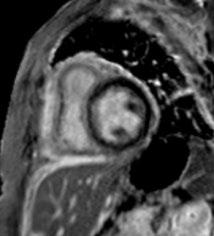

In contrast to acute complications, chronic complications are generally more unique to the Caesarean section itself, and are not typically seen with other surgical procedures, with the exception of incisional hernia. Caesarean scar niche was identified as an important cause of pain and irregular bleeding (Figure 1).

Figure 1: Caesarean scar niche.

C-section: Caesarean section; US: ultrasound.

Acute complications included injury to adjacent organs, bleeding, and haemorrhage, along with the risks associated with anaesthesia, typical of acute complications seen with most surgical procedures. The organs most at risk during a Caesarean section are the bladder, ureters, and bowel, due to their proximity to the uterus. Most of the postoperative collections observed were located anterior to the uterus in the uterovesical space, or wound infections in the subcutaneous tissue.

The complications identified in this local review of Caesarean section cases align with the recognised complications documented in the literature.

The purpose of this pictorial review is to depict the various complications associated with Caesarean sections, and their appearances on different imaging modalities using local cases.

While Caesarean sections are generally considered safe, there are a range of associated complications. With the increasing frequency of Caesarean sections, a corresponding rise in the incidence of complications can be expected. Therefore, it is important to ensure that radiologists can effectively identify the most common complications and their features across different imaging modalities.